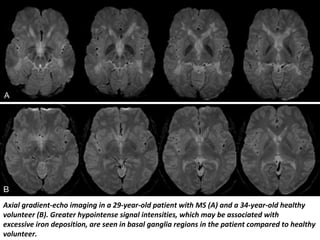

• Abnormal iron deposition is thought to be the

Axial gradient-echo imaging in a 29-year-old patient with MS (A) and a 34-year-old healthy

volunteer (B). Greater hypointense signal intensities, which may be associated with

excessive iron deposition, are seen in basal ganglia regions in the patient compared to healthy

volunteer.